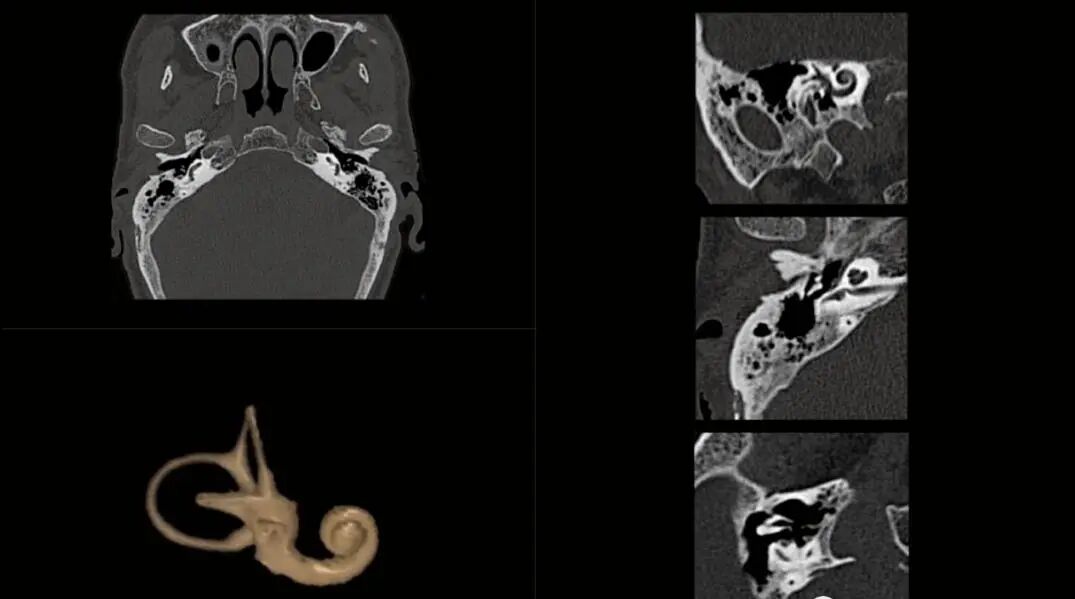

8、内耳CT成像:耳部ct可以显示外耳道的前、后壁,鼓膜,鼓室,听小骨组成的听骨链,前庭窗,耳蜗,半规管和前庭,前庭水管,内耳道。面神经管的迷路段和鼓室段以及咽鼓管骨性段等结构。通过耳部ct可以判断是否有先天性的外耳、中耳、内耳畸形。特别是前庭水管扩大,是内耳畸形中最常见的一种。